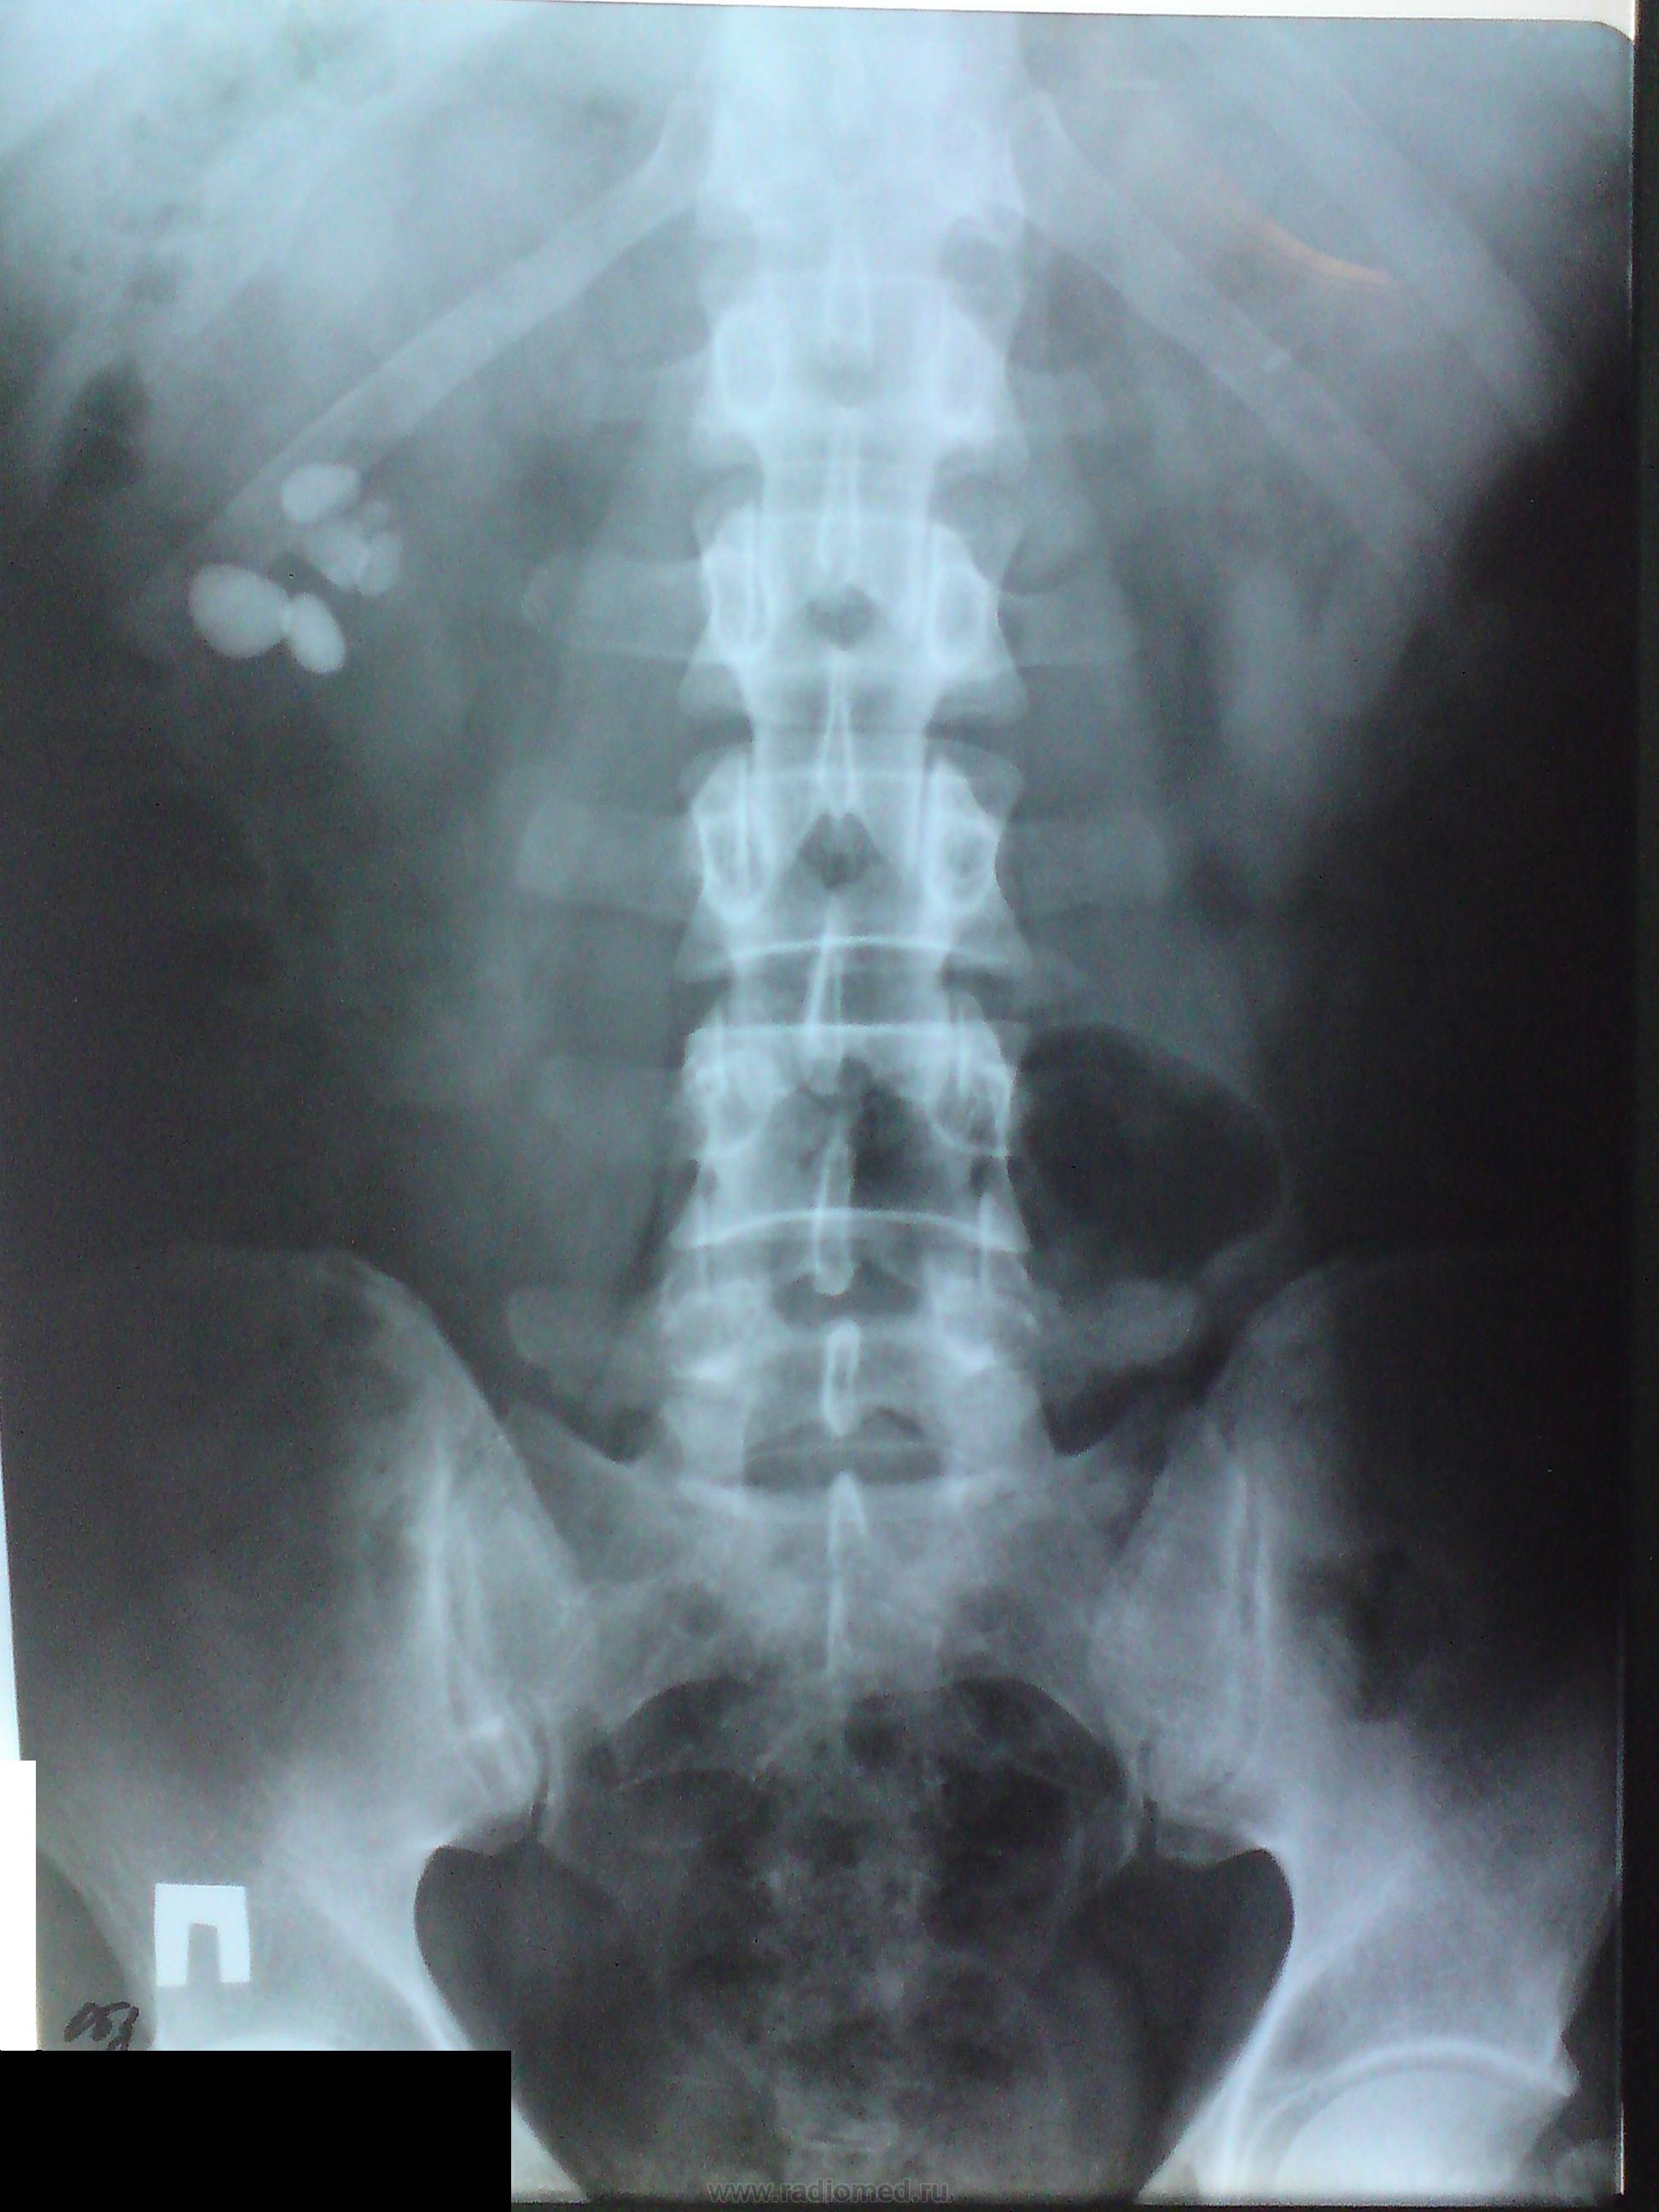

На первых 2 снимках пациент находится лежа и конкременты равномерно распределяются по ЧЛК, а вот последующие снимки стоя, где камни смещаются книзу.

На мой взгляд, хотя, и тени "конкрементов" хорошо визуализируются, и "кричат" - "вот мы", но они не являются главными в "раскрутке" теневой картины. Мне кажется, что на первое место, в данной ситуации выползает, на первый взгляд малозначимый симптом - характеристика контура поясничной мышцы справа.

Четко дифференцирующийся контур поясничной мышцы в верхних отделах становится размытым и не видимым в нижних отделах. Следовательно, он перекрыт чем то мощным или большим (увеличенным) по сравнению с указанной мышцей.

Что "это"? может быть резко расширенный мочеточник в результате конкремнта в дистальной трети мочеточника, стриктуры, опухолевого роста, который может иметь место и извне мочеточника.

Именно на уровне почечной лоханки контур поясничной мышцы перестает дифференцироваться, а следовательно, все, что ниже резко расширено, а может, что менее вероятно "проросло".

Второй по значимости скиалогический симптом, на мой взгляд, в данном случае - это отсутствие дифференциации контуров правой почки. Я не даром задал вопрос была - ли травма справа, которая могла "включить" и травму почки. О травме свидетельствуют множественные консолидированный переломы ребер. И в данном случае, при расшифровке скиалогической картины, учет анамнеза, будет иметь, отнюдь, не последнее место.

У пациента была проведена холецистэктомия,поэтому желчный пузырь отпадает. По УЗИ множественные конкременты правой лоханки,с деформацией ЧЛК, слева конкремент ЧЛК без структурных изменений. Вот на счет травмы анамнез не собирал, пациента готовят на операцию. После чего выложу результаты.